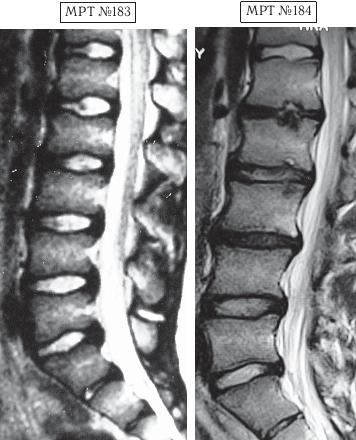

На МРТ № 183 наблюдается состояние поясничного отдела позвоночника — начальная стадия развития остеохондроза практически во всех сегментах позвоночника. На МРТ № 184 того же пациента — состояние поясничного отдела позвоночника после активного укрепления мышц спины физическими упражнениями (кинезитерапии): спондилёз, грыжи Шморля в сегментах ТXII—LI, LI—LII, LII—LIII, практически полное отсутствие межпозвонкового диска в сегменте L–Lu, значительное снижение высоты межпозвонковых дисков в сегментах LII—LIII, LIII—LIV, исправление физиологического лордоза, стеноз спинномозгового канала. Кроме того, помимо всего вышеперечисленного у пациента на уровне поражённых сегментов развился спондилоартроз. |